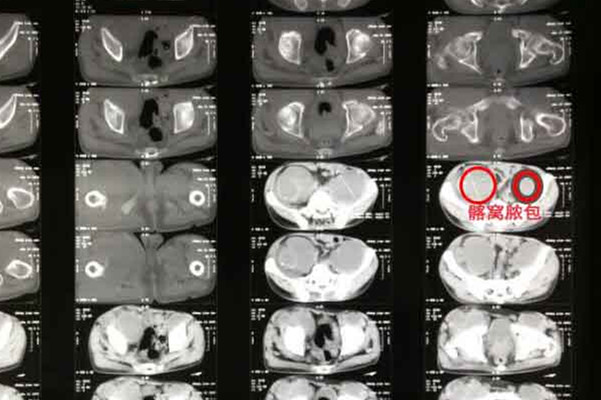

该患者经该方案治疗一段时间以后,血沉速度明显下降,体温恢复症状,脓肿吸收加快,骨密度恢复良好。整个精神状态也恢复往常,真正意义上达到了标本兼治的作用。